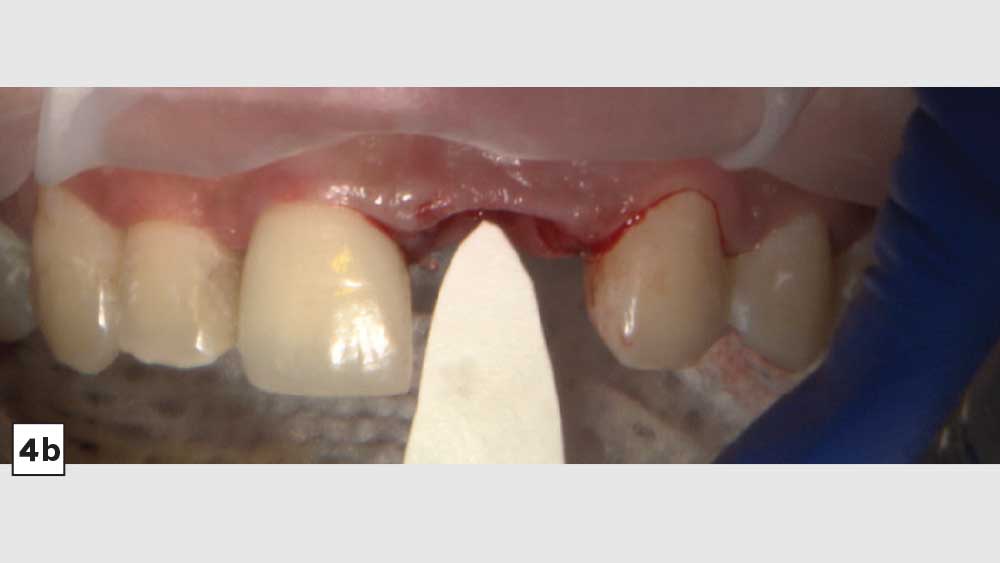

BRIDGING THE GAP WITH BRUXZIR® ESTHETIC

After conducting a thorough diagnostic examination, a vertical root fracture was noted, leaving the #9 central incisor malaligned and unstable. Due to the presence of significant vertical bone loss, extensive treatment for guided bone regeneration and a connective tissue graft would have been required prior to implant placement. After the patient was consulted on these factors, she opted against implant treatment. Once we discussed the remaining options, she decided on a bridge from #8–11 and a veneer on #7. Because she was congenitally missing tooth #10, placing a bridge to restore the edentulous area required preparing the adjacent canine and reshaping it to look like the missing lateral. I selected BruxZir® Esthetic Solid Zirconia as the best material to restore her beautiful smile. Not only does BruxZir Esthetic have superior strength compared to similar all-ceramic materials such as IPS e.max®, but it also has a translucent, natural-looking appearance. Sometimes clinicians think it is risky to do an all-ceramic bridge, but with a strong material like BruxZir Esthetic that has an average flexural strength of 870 MPa, doctors can confidently seat an anterior bridge that will produce long-lasting results. BruxZir has become such a popular material for dentists that it has been utilized to successfully fabricate more than 1.2 million bridges.